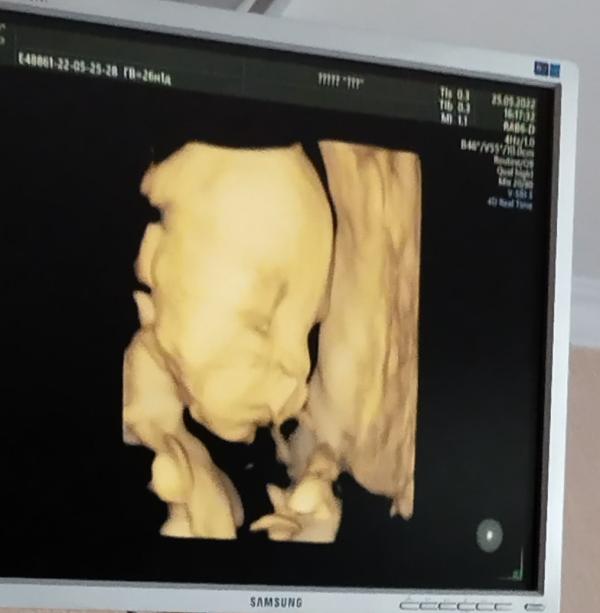

Оставлю тут фото на память,от старшей дочки потеряла такие фото,от маленькой ягодки бы оставить,25 неделек было,когда делали фото🤩

Моя ягодка,так похожа на старшую дочку,я поям видела когда докторица водила датчиком,все черты схожи , будет вторая малая копия папули❤️😍🍓